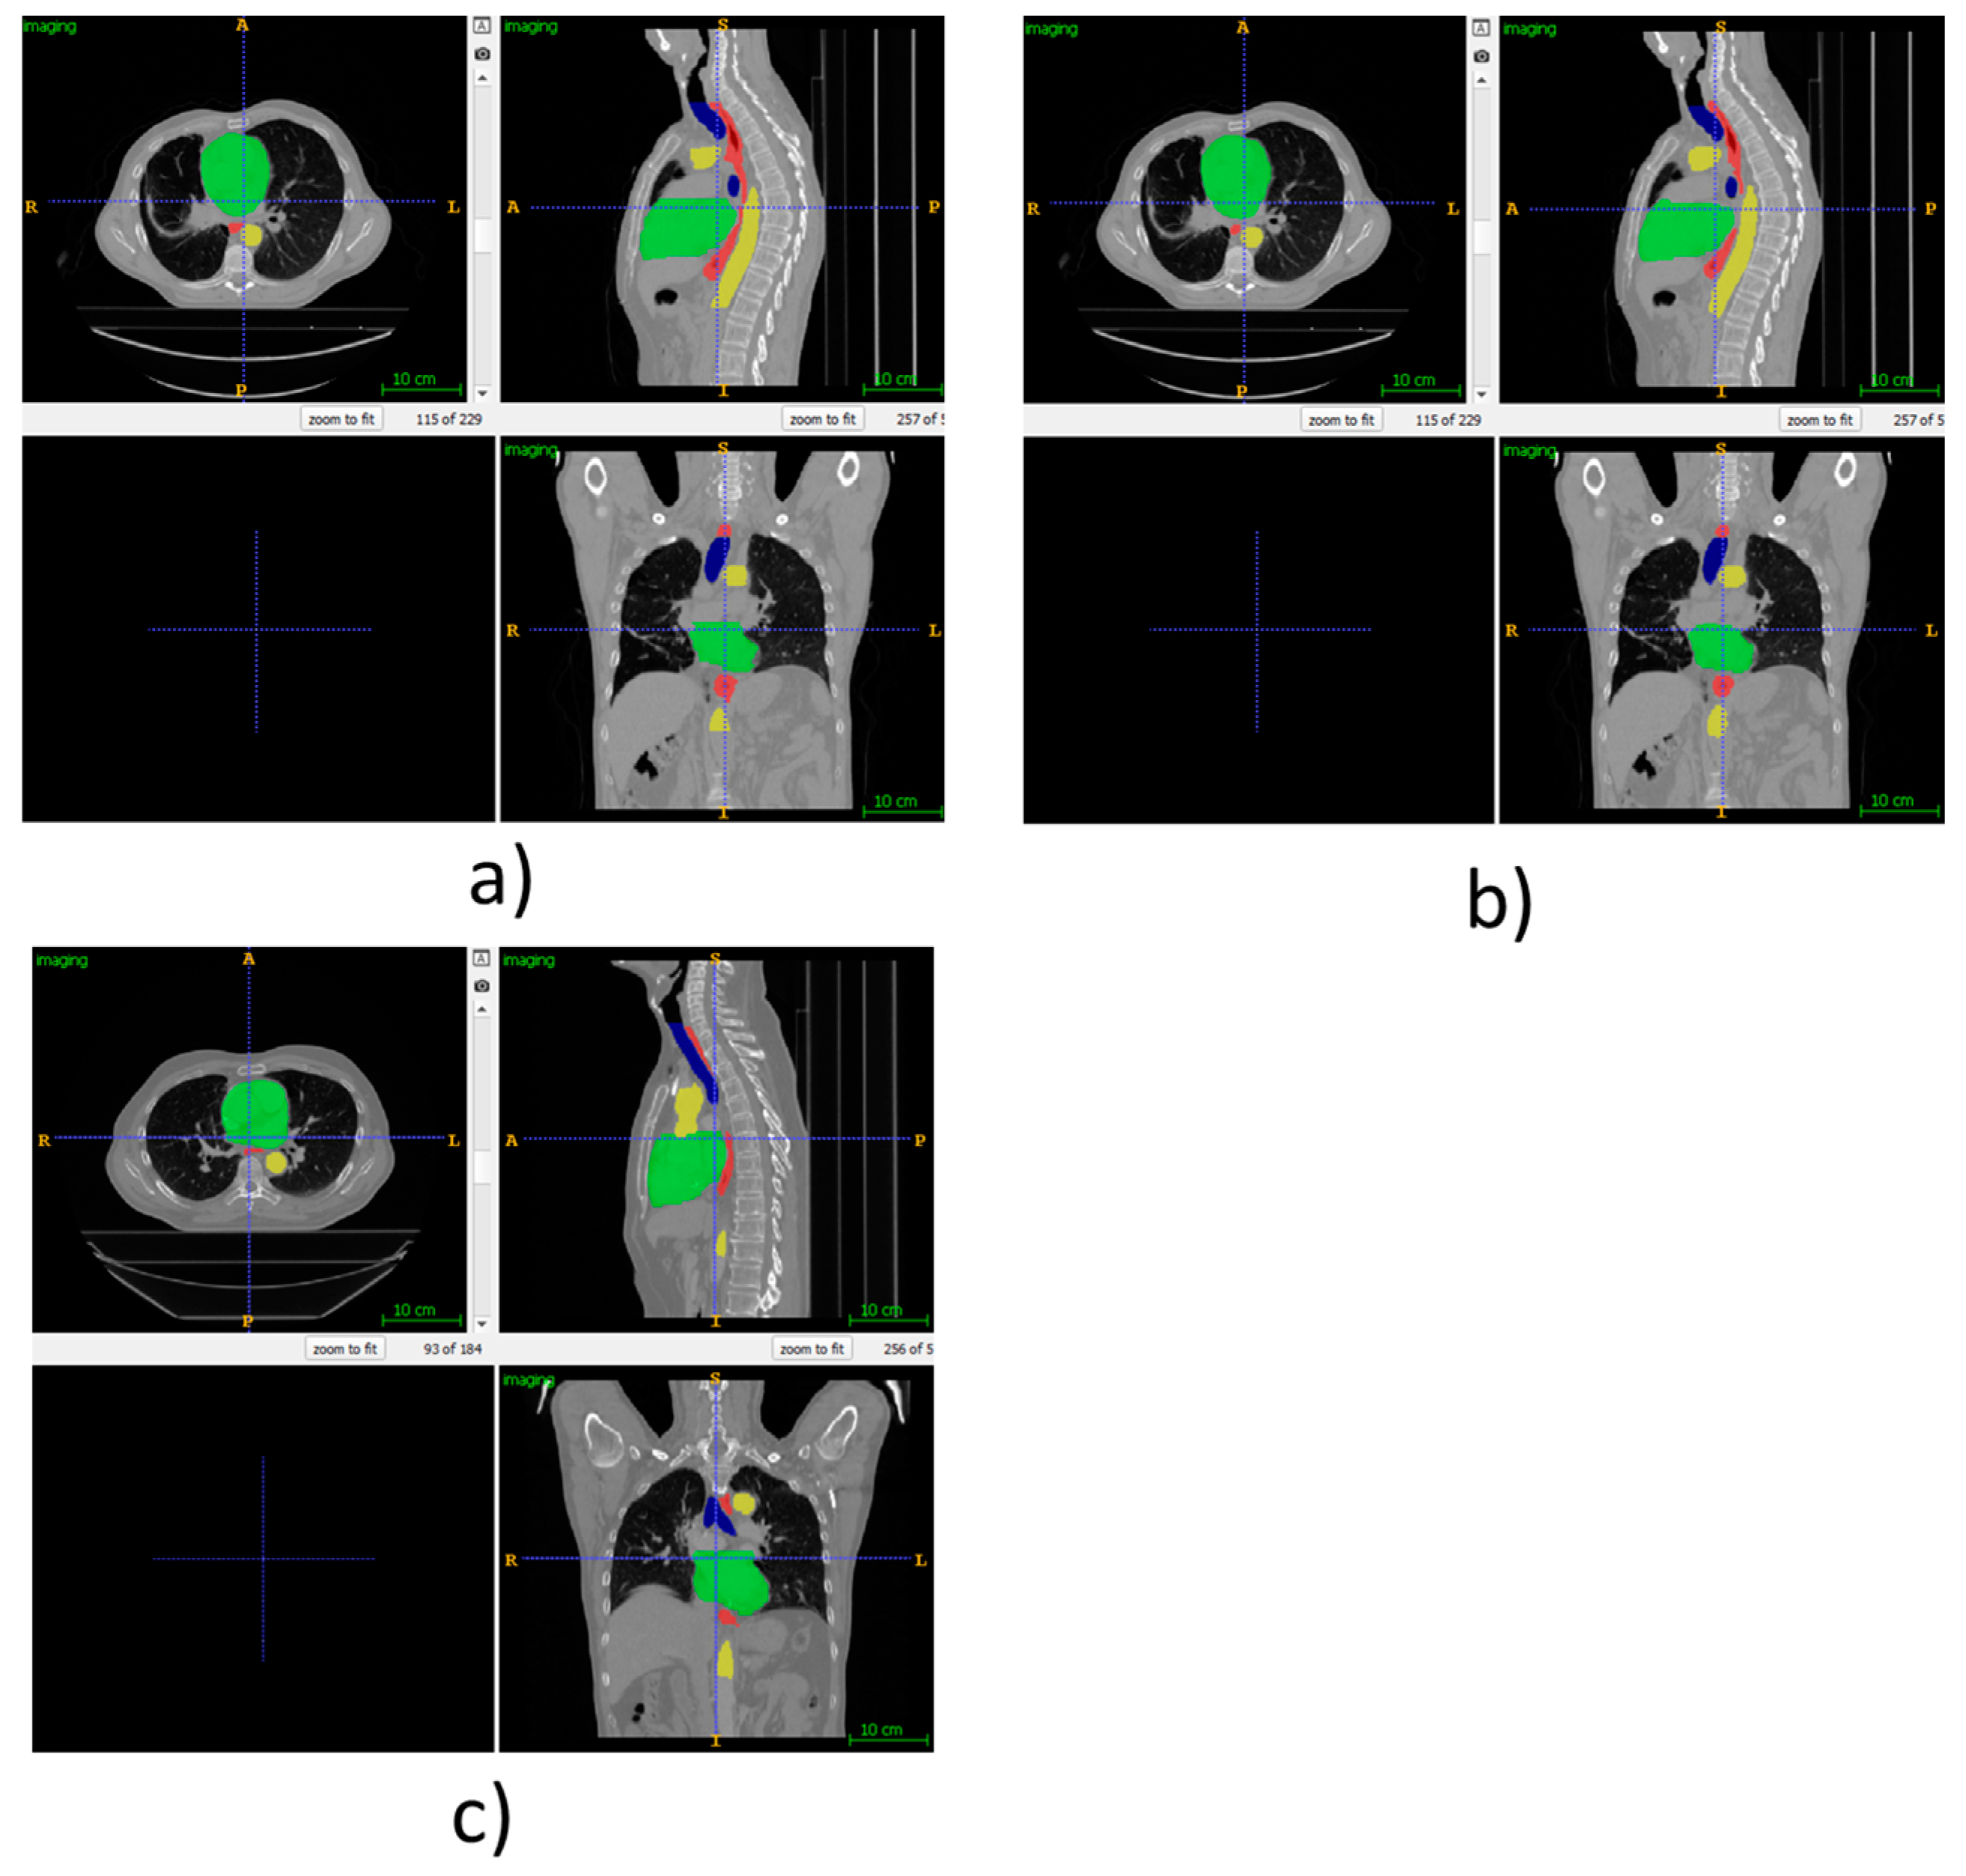

As visual examples, we have provided Figure 3, which shows the automatic segmentations using our proposed method for some of the patients from the SegTHOR dataset. For patient 01, the ground truth is provided as this is part of the training set. However, for patient 41, only our own segmentations are provided, as the ground truth is private to the SegTHOR team and is used in ranking the submissions.

Figure 3.

(a) Ground truth SegTHOR patient 01, (b) automatic segmentation using our proposed method for SegTHOR patient 01, (c) automatic segmentation using our proposed method for SegTHOR patient 41.